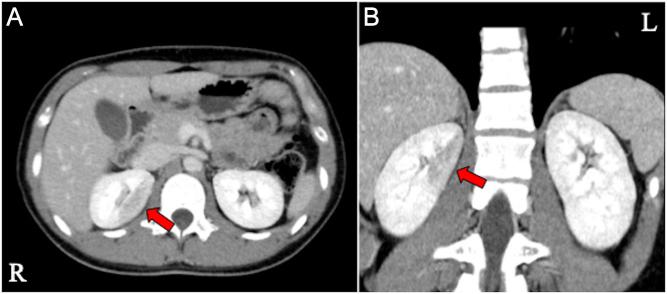

Segmental low-density area on contrast-enhanced CT is a possible clue to diagnosing branch artery fibromuscular dysplasia.

Fibromuscular dysplasia can cause renovascular hypertension. Since fibromuscular dysplasia may be underdiagnosed, precise diagnosis and management are crucial, especially for young women. A 20-year-old woman with hypertension and hypokalemia was referred to our hospital for further evaluation of secondary hypertension. At the previous hospital, her blood pressure was 160/110 mmHg and the serum potassium level was 2.9 mEq/L. The equilibrium phase on contrast-enhanced computed tomography revealed a low-density area in the upper median portion of the right kidney. On admission to our hospital, her blood pressure was 141/96 mmHg under 5 mg of amlodipine. Laboratory tests revealed plasma renin activity of 11.3 ng/mL/h and plasma aldosterone concentration of 117.1 pg/mL. Renal venous sampling of active renin concentration showed a right-to-left renin ratio of 3.13, confirming a significant increase in renin secretion from the right kidney. Selective reno-angiography detected focal stenosis with adjacent aneurysmal dilation and tortuosity in the proximal branch of the right renal artery. She was diagnosed with branch artery fibromuscular dysplasia and successfully treated with percutaneous transluminal angioplasty. After the treatment, she was free from hypertension and hypokalemia without any medications. Since branch artery fibromuscular dysplasia is sometimes difficult to diagnose, contrast-enhanced computed tomography can be a promising diagnostic tool as shown in this case. Concerning treatment, our patient was treated with percutaneous transluminal angioplasty, which should be considered for women of reproductive age because recommended antihypertensive medications can be teratogenic even in the first trimester of pregnancy.

Although branch artery fibromuscular dysplasia (FMD) is sometimes difficult to diagnose, it should be considered in patients with high-renin, high-aldosterone hypertension. Branch artery FMD can present with a low-density area of the kidney on contrast-enhanced computed tomography, as shown in this case. Percutaneous transluminal angioplasty (PTA) can be an appropriate treatment for branch artery FMD, especially in young female patients. PTA may immediately improve hypertension and hypokalemia without the need for medications.